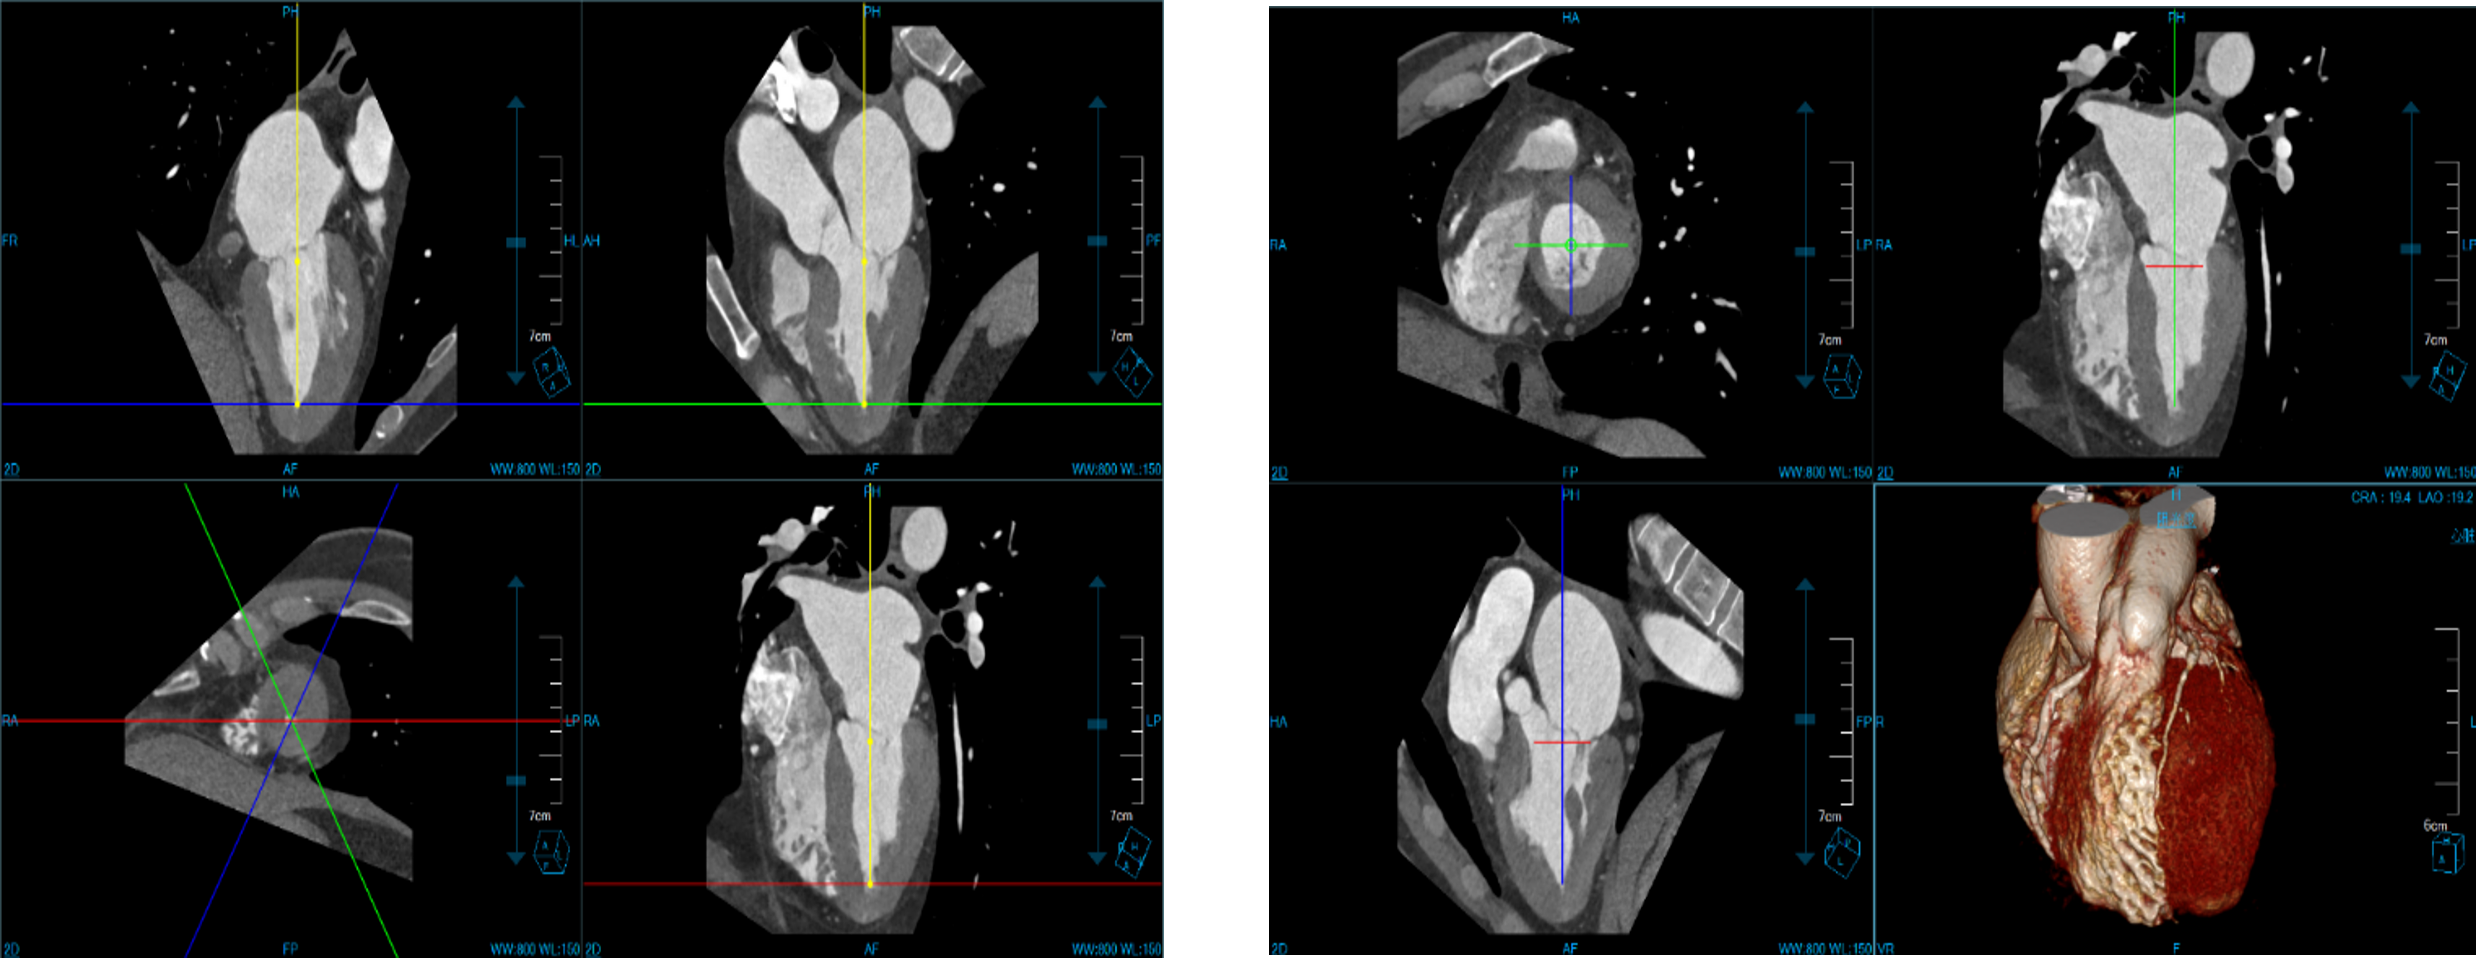

Cardiac Viewer Images

View heart images of each phase, execute three-dimensional reconstruction and heart extracted for CT heart images, and then view patient heart by more intuitive way, diagnosis various cardiovascular diseases.

• Different phases data comparison

• 4D play

• Oblique MPR display

Cardiac Function Analysis

Analyze a variety of heart functions

• Left ventricular volumes Ejection fraction

• Left ventricle wall motion and thickening

• 4D Rendering

One Station Cardiac Diagnosis Analysis

Prospective ECG-triggered Mode Advanced Diagnosis-guided solution –ECG guided Cardiac Examination